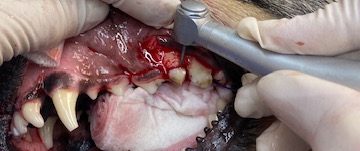

Upper premolar (208) extraction technique in photos

Slab fracture of 208x-ray at 45 degreesno sign of granuloma but as slab is below the gum line the tooth needs to be extractedInfraorbital and maxillary nerve blocks placedAll teeth descaled and polishedIncise to gingival junction with scalpel to distal edge of 209Place thumb on on infraorbital canal and make vertical incisionRaise a gingival flap using periosteal elevatorRound bur #6 to bur away buccal alveolar boneThe tooth sectioned at the furcationCrown removed and gutters cut using taper fissure burVet tome used to aid with extraction of distal root. Elevators and luxators also usedDistal root removed when looseDistal rootCrown height reduce on mesial roots until furcation visibleFurcation visibleBuccal root extracted with elevatorsTaper fissure bur used to remove the buccal bone of palatal rootPalatal root extracted using luxators, elevators and forcepsX ray to ensure all roots completely extractedRounded ends on sectioned roots indicate the root is fully removedCurette socketsFlush sockets with salineSmooth alveolar bone to ensure no rough edges with diamond football burMake periosteal releasing incision in the flap to ensure tension free closureSuture with 4/0 absorbable material simple interrupted patternClose up of extraction site after suturing